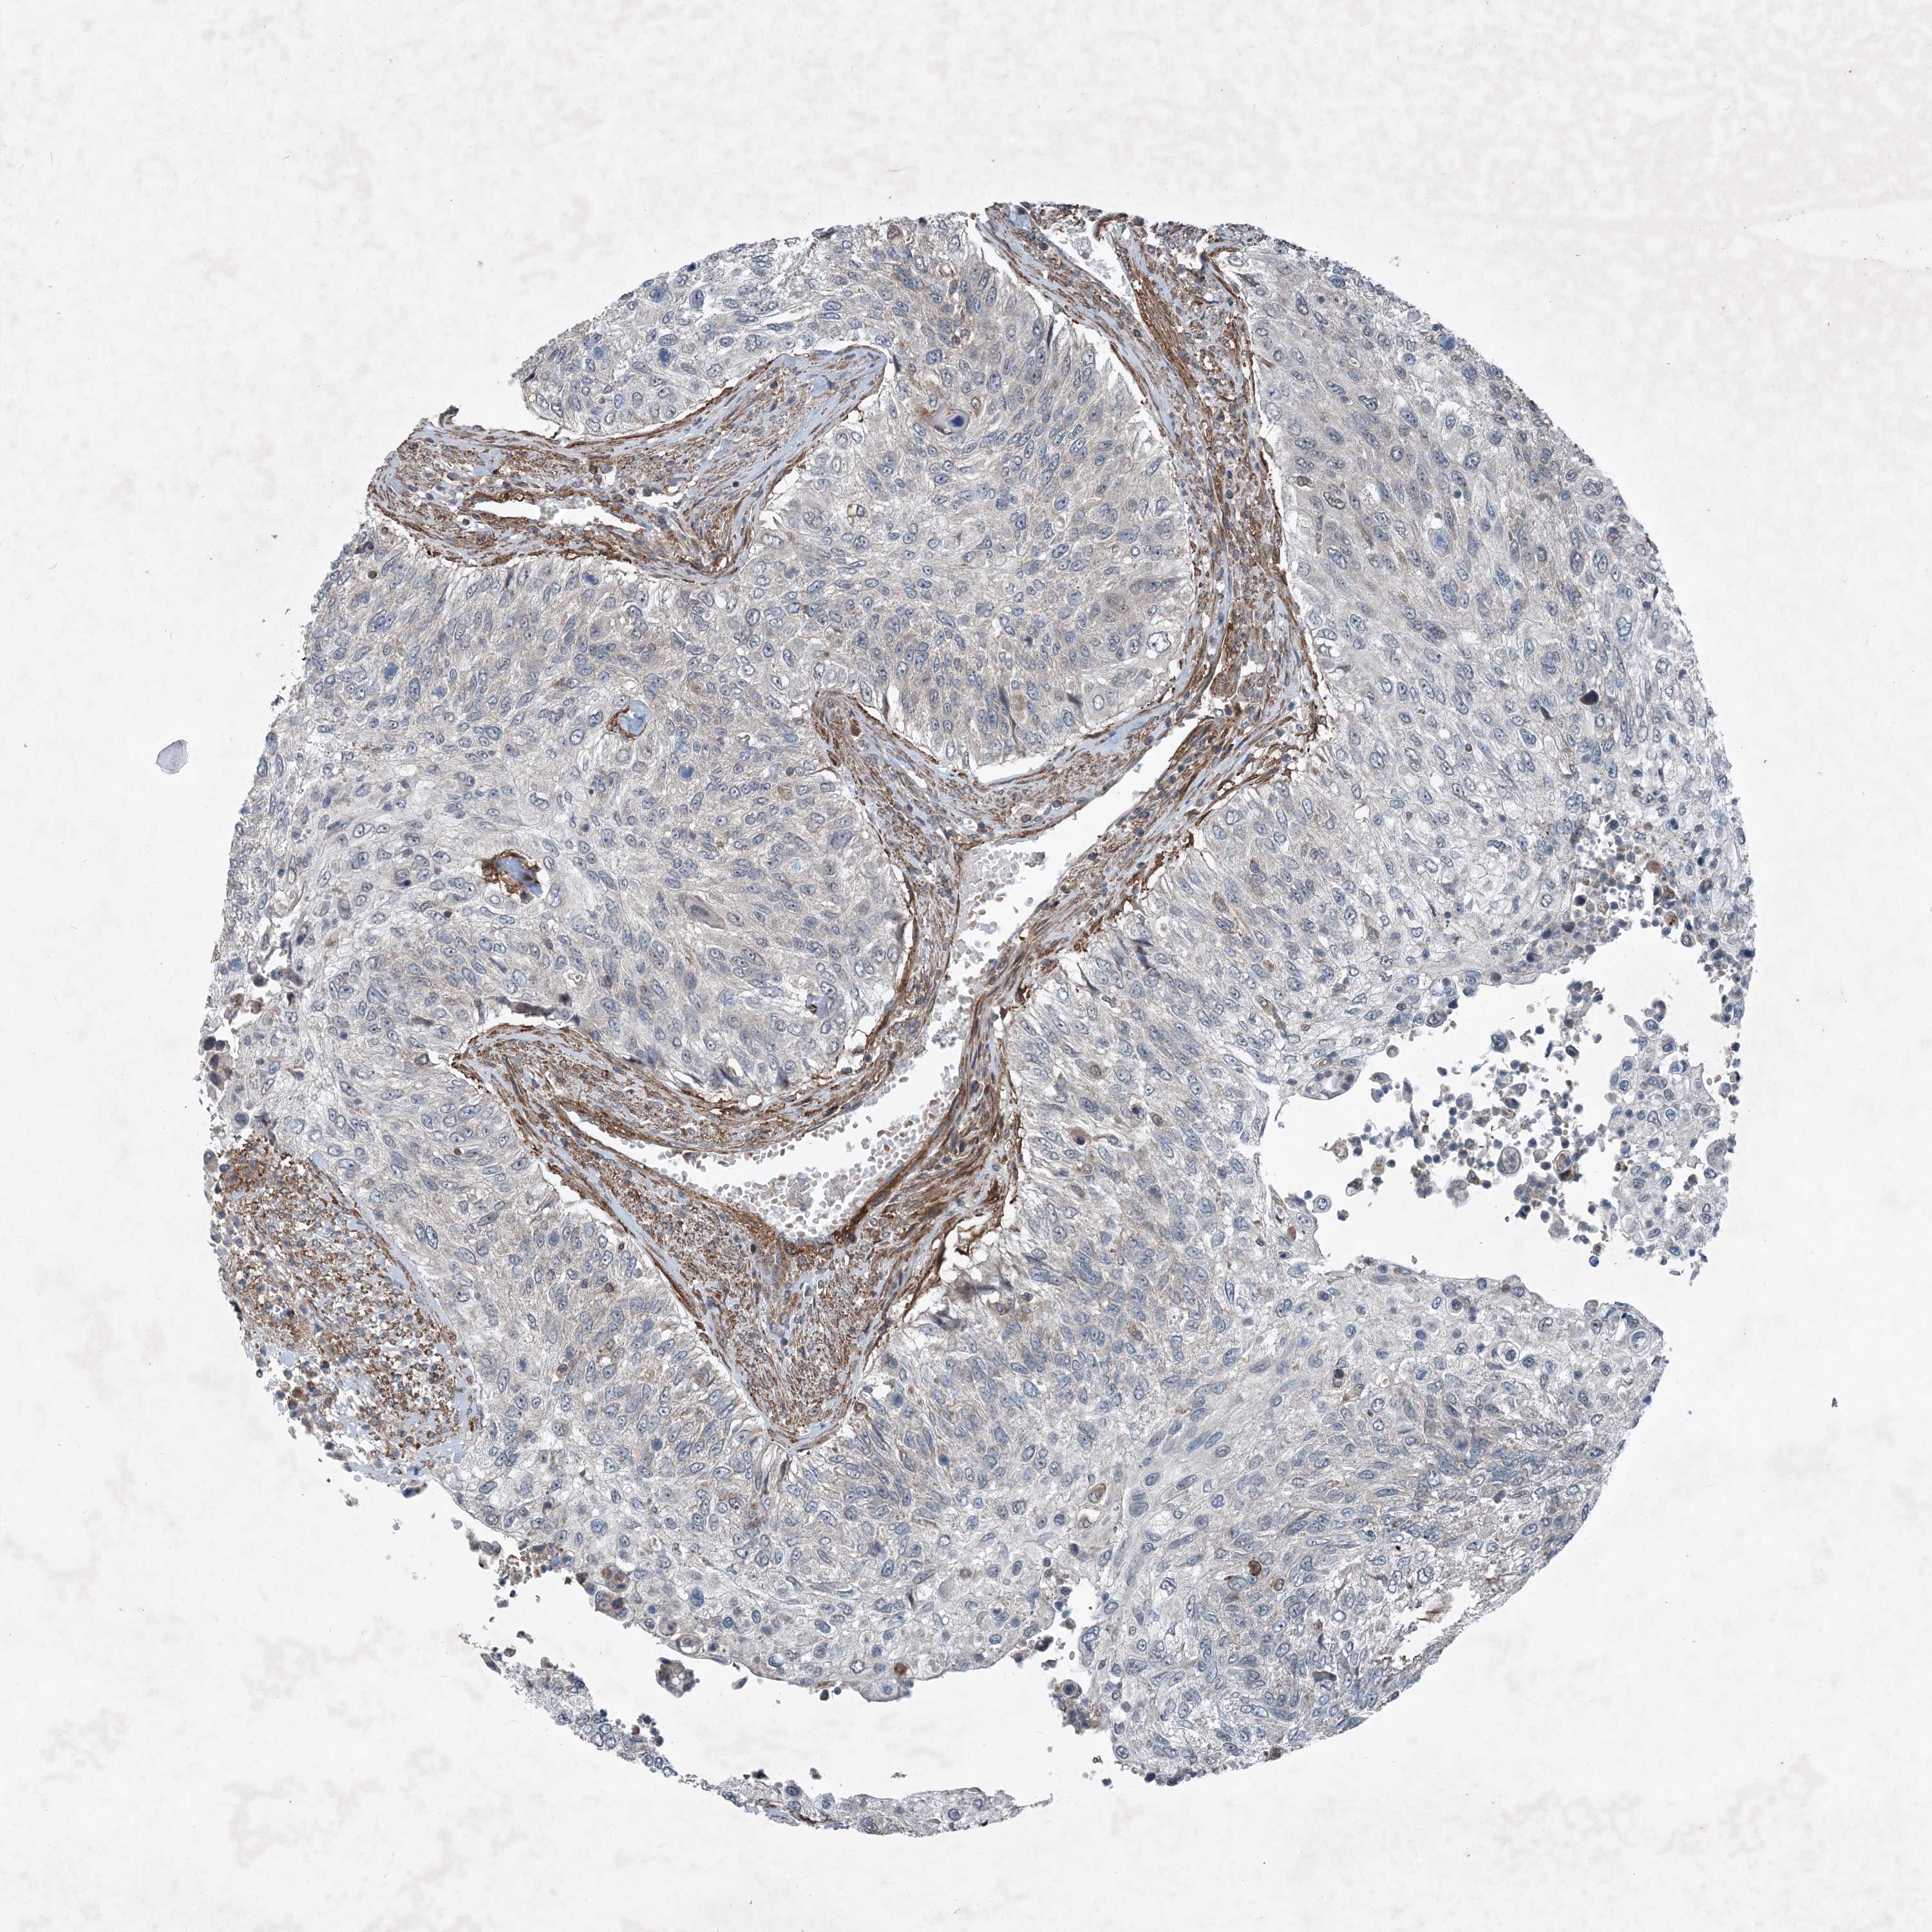

UROTHELIAL CANCER - Protein expressioni

A mouse-over function shows sample information and annotation data. Click on an image to view it in a full screen mode. Samples can be filtered based on level of antibody staining by selecting one or several of the following categories: high, medium, low and not detected. The assay and annotation is described here.

Antibody stainingi

Antibody staining in the annotated cell types in the current human tissue is reported as not detected, low, medium, or high, based on conventional immunohistochemistry profiling in selected tissues. This score is based on the combination of the staining intensity and fraction of stained cells.

Each image is clickable and will lead to virtual microscopy that enables deeper exploration of all samples and also displays staining intensity scores, fraction scores and subcellular localization as well as patient and tissue information for each sample.

Antibody HPA035933

Staining

High

Medium

Low

Not detected

Intensity

Strong

Moderate

Weak

Negative

Quantity

>75%

75%-25%

<25%

None

Location

Nuclear

Cytoplasmic/membranous

Cytoplasmic/membranous,nuclear

Urothelial carcinoma, Low grade